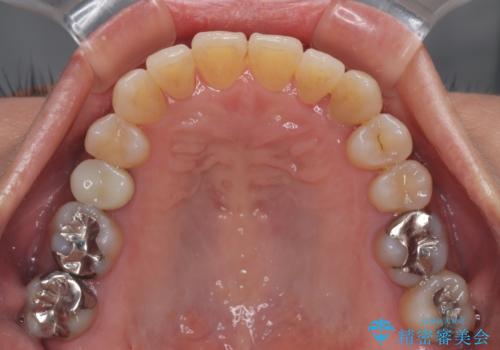

受け口と八重歯を改善 インビザライン矯正治療

- 前歯のデコボコや八重歯を治したいとのことで来院された患者様です。

受け口傾向の骨格であり、前歯はクロスバイトまたは切端咬合となっており、下顎を中心に歯列全体の後方移動を行い、IPR(歯と歯の間を削る)によってデコボコが解消するように設計し、インビザラインにより治療を行うこととしました。

受け口傾向のインビザライン矯正は比較的治療を行いやすいため、きれいに仕上げることができました。舌の突出癖が顕著であったため、改善のためのトレーニングをしっかりと行っていただきました。